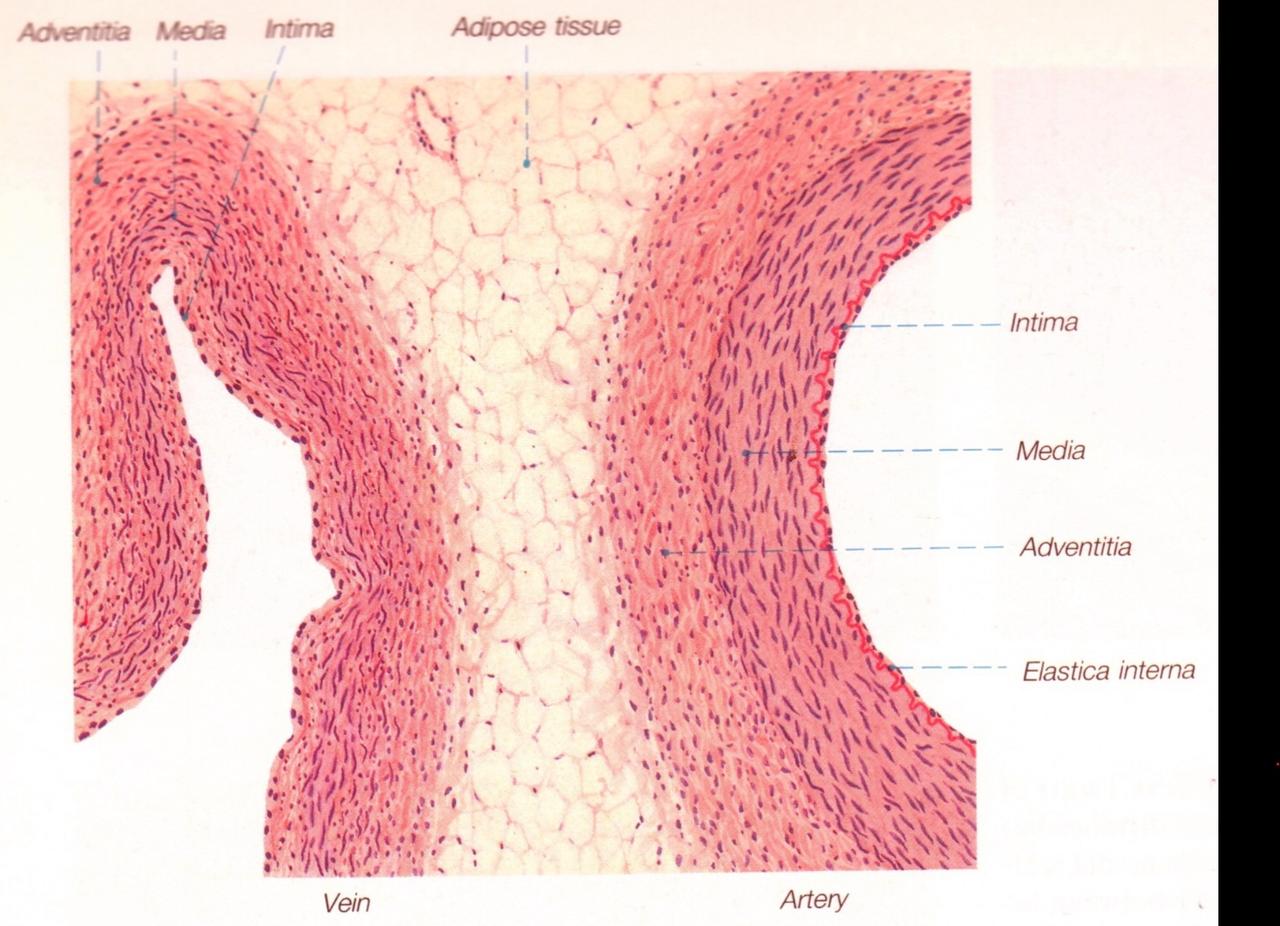

Fig 3.43: Opbouw van grotere bloedvaten

|

|

Fig 3.44: Opbouw van verschillende types arterien

A arteriool (< 500 um)

B musculaire arterie (rode kleur)

C elastische arterie (gele kleur, bv. aorta)

-

tunica intima

lamina elastica interna -

tunica media

gladde spiercellen elastinevezels

lamina elastica externa -

tunica adventitia

|

|

Fig 3.46: Opbouw van venen

-

< 50 um

-

50 - 200 um

-

> 200 um